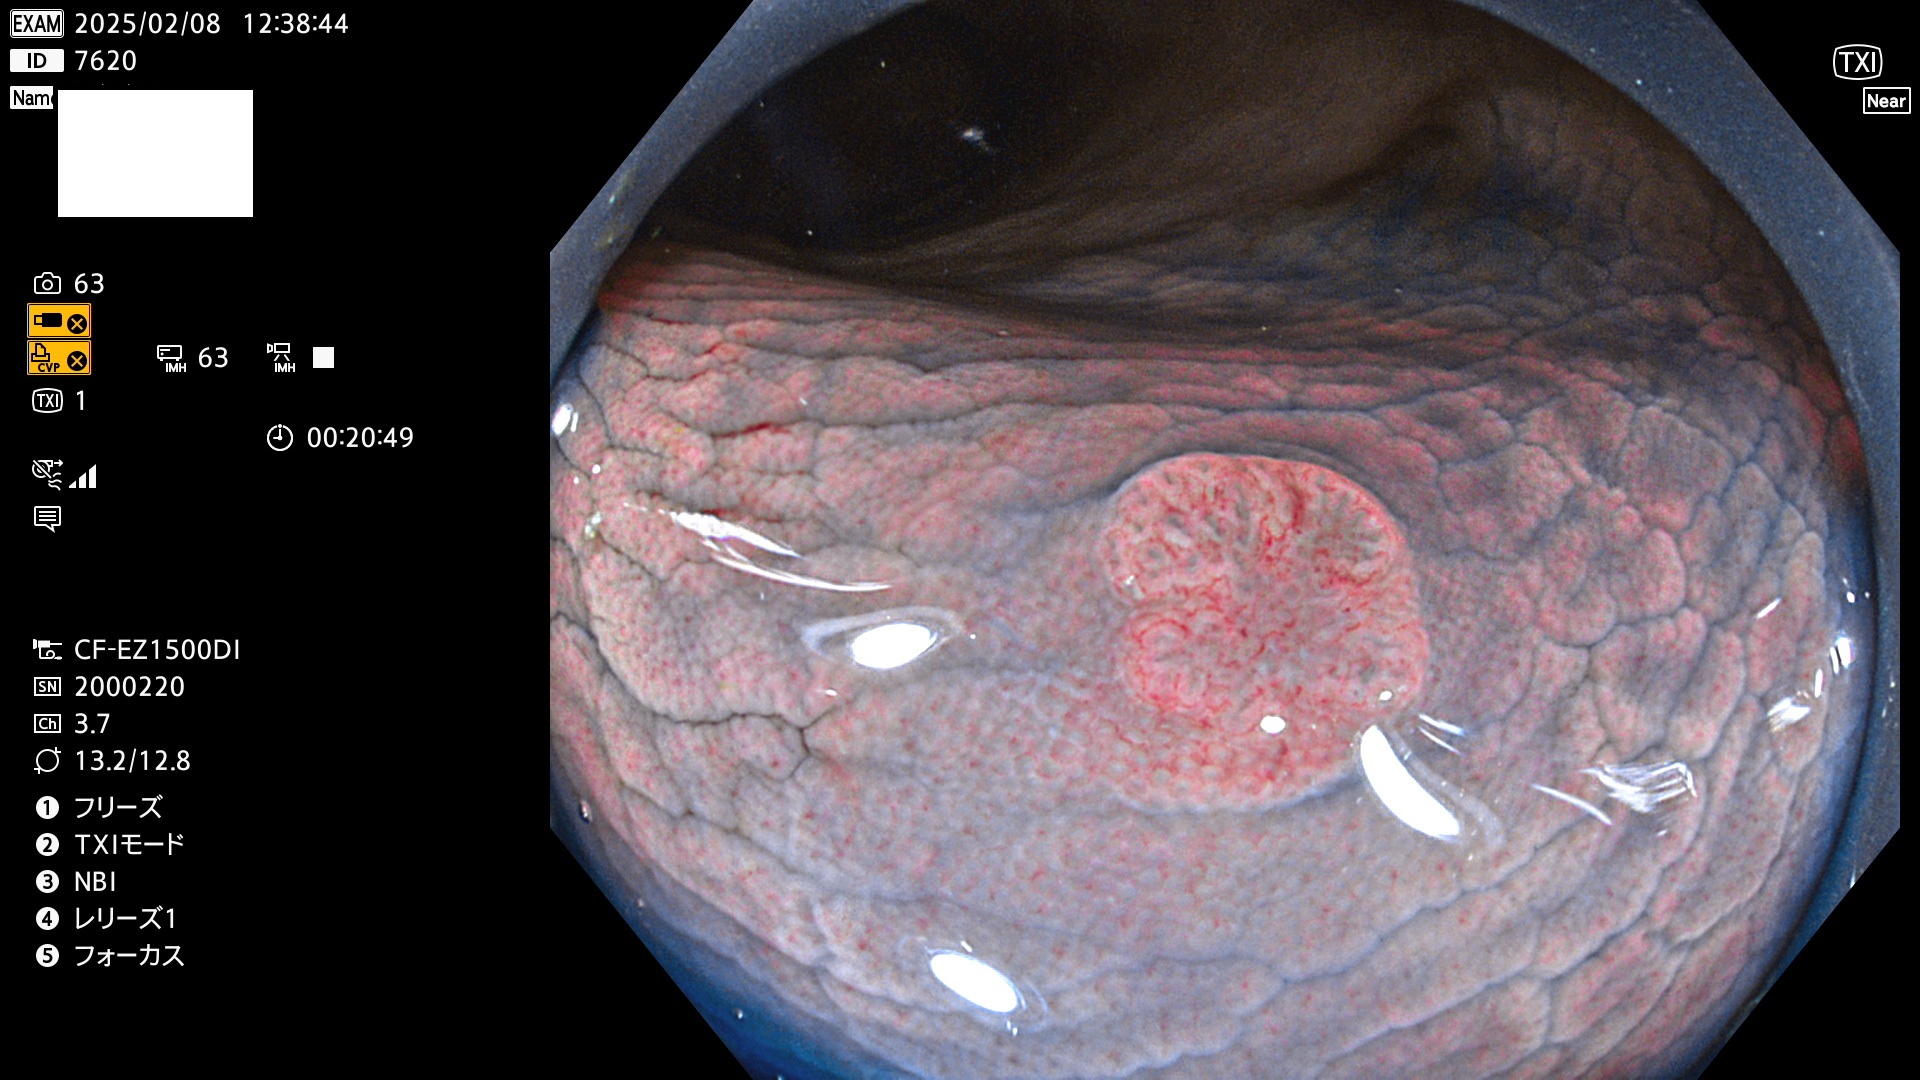

今週のUb、Uc型腺腫

完全に平坦な物をUb、陥凹している物をUcと呼びます。最も発見が難しく危険な病変です。

毎週の検査(木・金・土・日)に発見されたUb、Uc型・腺腫を、その週の日曜の夜にUPし1週間、提示します。

抽出の対象期間 2025年2月6日〜2月9日の4日間(48件の検査)7個 (7/48=14%)